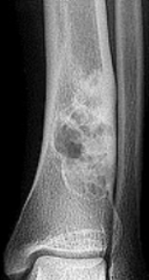

What type of lesion is this? | Giant cell tumour |